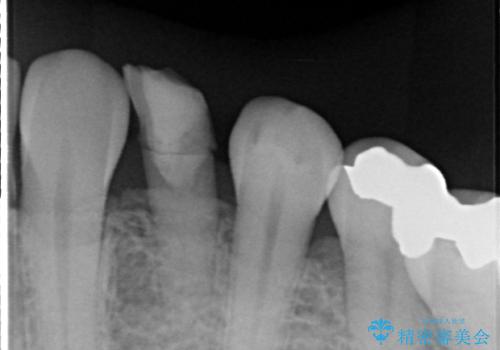

診査の結果、左下に残存していた乳犬歯が水平的に破折しており、残念ながら保存は困難な状態でした。

そこで今回は、抜歯と同時にインプラントを埋入する「抜歯即時インプラント治療」をご提案。

外科処置の回数を抑え、治療期間を短縮できる点が大きなメリットです。